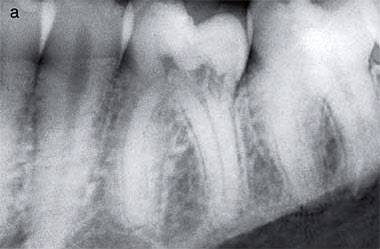

film ของฟันหลัง ที่เจอ Invasive cervical resorption Class 2

ในคลินิก มองไม่เห็นความผิดปกติใดๆ (ไม่มี discoloration)